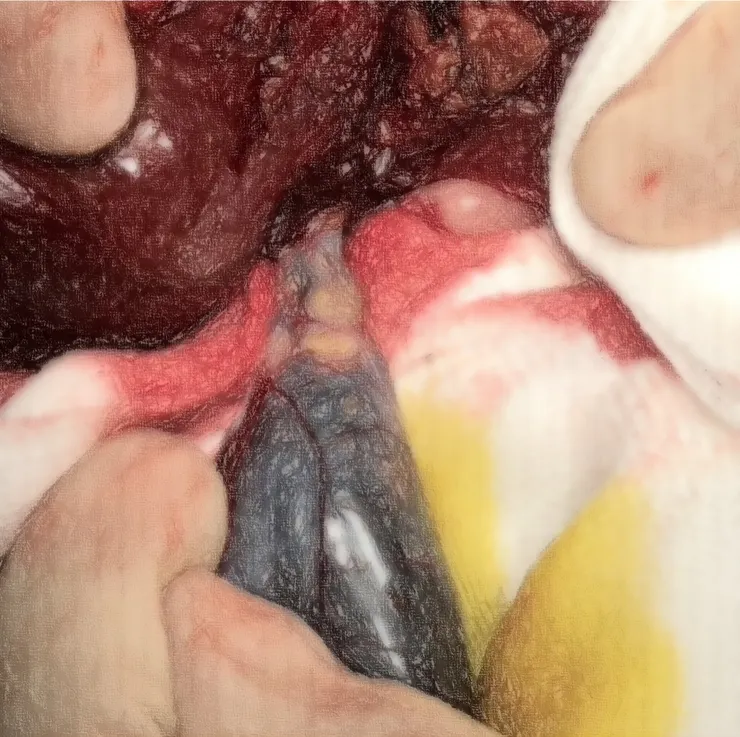

考慮到今年跟膽囊似乎有緣,轉來手術切除得有點多。

在這次膽囊摘除的孩子要住滿三天準備出院的當下